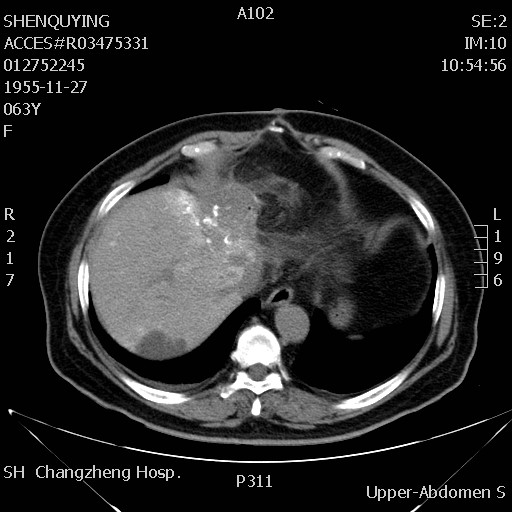

影像学检查:

腹部MRI:

检查时间:2018年10月19日

影像图谱:T1

2018年10月18日基线扫描,腹部MRI提示:左肝切缘见一长径约5cm的类椭圆形复发灶,与胃壁及十二指肠降段关系密切,后腹膜见肿大淋巴结。胸部CT未见明显转移征象。